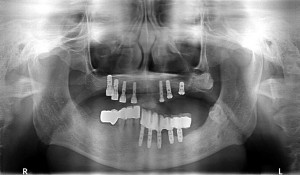

50歳代男性

上顎が何本か残っておられましたが全て動揺があり、抜歯が適当かと思われましたので、抜歯させて頂き、

総入れ歯を当院にて装着させて頂いた人でした。

抜歯後、4か月程経過しましたので、スイス製ストローマンインプラントRNを7本埋入させて頂きました。

左上顎洞底は薄かったため、ソケットリフトを併用させて頂きました。

5カ月後ぐらいに最終補綴物を装着する予定です。

術前

術後